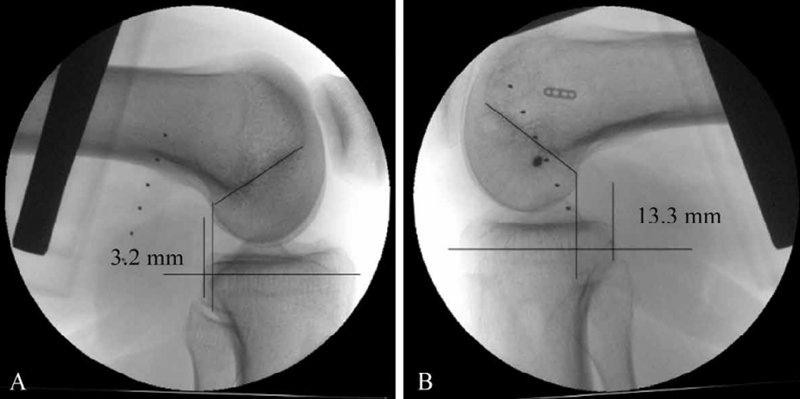

收藏后交叉韧带损伤的诊断